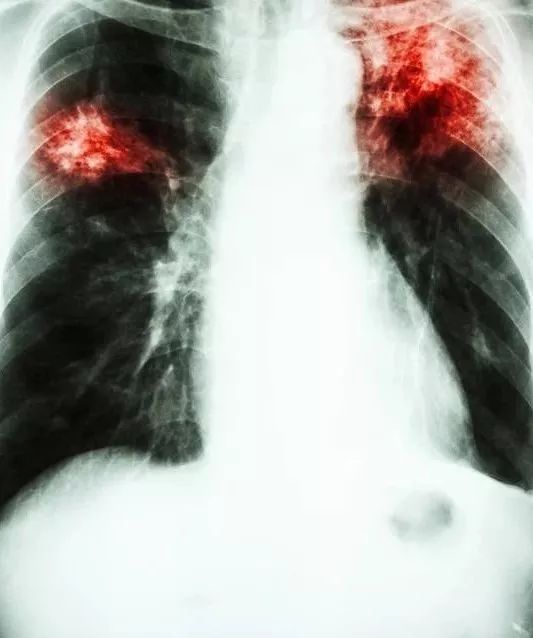

肺结核是一种生长比较缓慢的微生物,有时候在营养适合的培养基上,也要长一两个月才能长出一个明显的菌落,不过虽然生长缓慢,但其致病性非常厉害,全身上下的各个组织,包括骨头都可能被结核菌侵犯甚至毁坏,我们知道不同的病原体会引起不同的病变,像有一些病原体只会引起肺部的渗出,不会毁坏废物的正常结构,比如说肺炎链球菌,导致了大叶性肺炎,其来势汹汹,但是经过治疗之后会不可以完全恢复,甚至不留下痕迹。但结核菌就不一样了,所到之处造成的损害,大部分是以坏死为主,甚至骨关节,感染结核之后,如果得不到及时的治疗,整个骨关节的结构都有可能被毁坏形成一团泥沙,在肺部则主要形成空洞,严重的肺结核,可以使大部分肺失去功能,形成大大小小的空洞,被称为毁损肺。